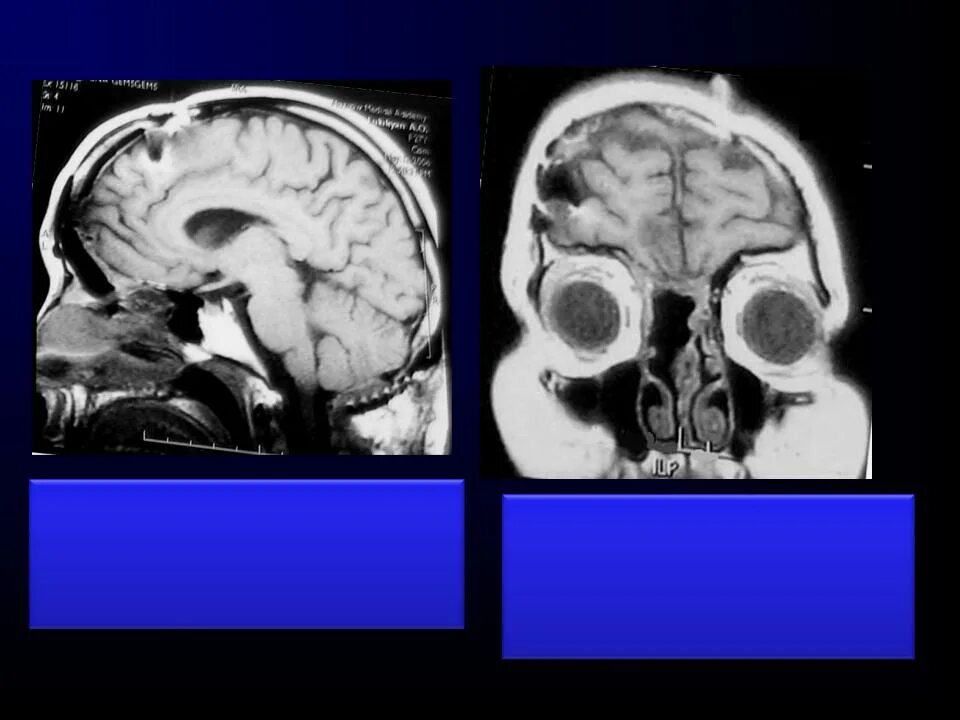

Отек головного мозга мрт